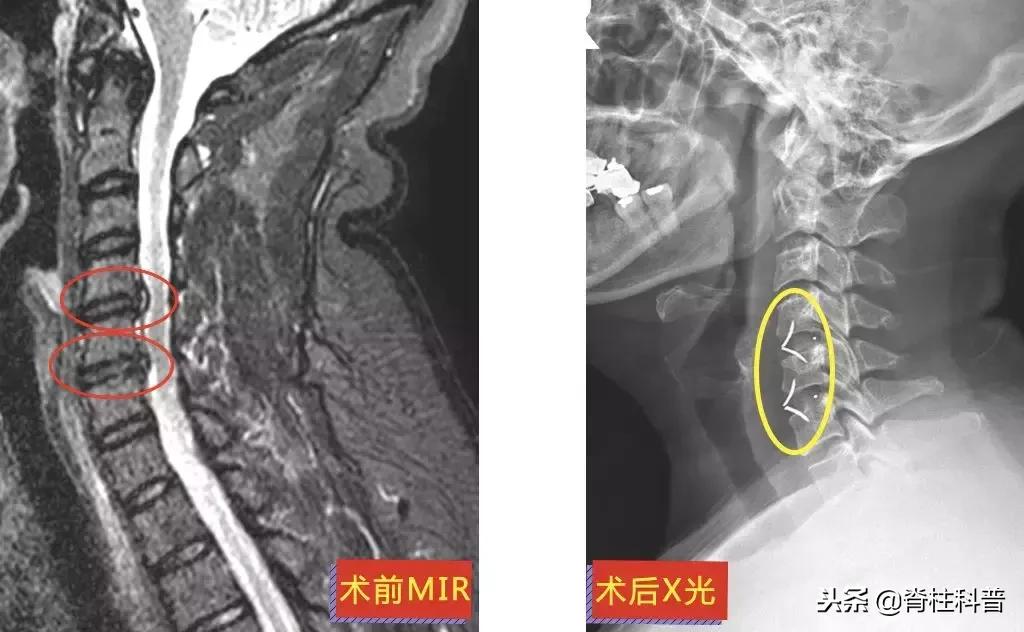

和大部分病人一样,为了避免手术治疗,他们都“竭尽所能”。牵引、针灸、推拿治疗是常见的保守治疗方法,保守治疗的效果如何,需要根据不同的病情来做判断,在此按下不表。下面这位黄三叔经过“脱水治疗”,却是效果欠佳。

▲ 黄三叔:术前MRI与术后X光